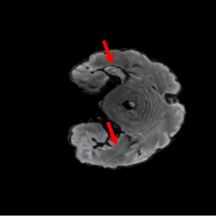

5.3 Out-of-Domain Generalisation

One way to test the generalization capability of the trained X-Diffusion is to test it on a completely different domain from an MRI dataset not seen during training. We report the single-slice results on NYU fastMRI [37, 82], a knee MRI dataset, using the X-Diffusion trained on the BRATS brain MRIs. The results are shown in Figure 9 and Table 2. It shows how successfully X-Diffusion is able to generate knee MRIs from a single image, despite not seeing knees at all in training. To qualitatively assess how realistic our generated 3D volumes were (produced from a single slice), we gave 20 generated examples alongside their real MRI counterparts to an expert orthopaedic surgeon. He was then asked to identify the real example from a given pair. The surgeon identified with certainty only 10 real knee MRIs out of 17, while could not decide on the remaining 3 of the 20 MRI pairs. This further validates the generated out-of-domain MRIs.